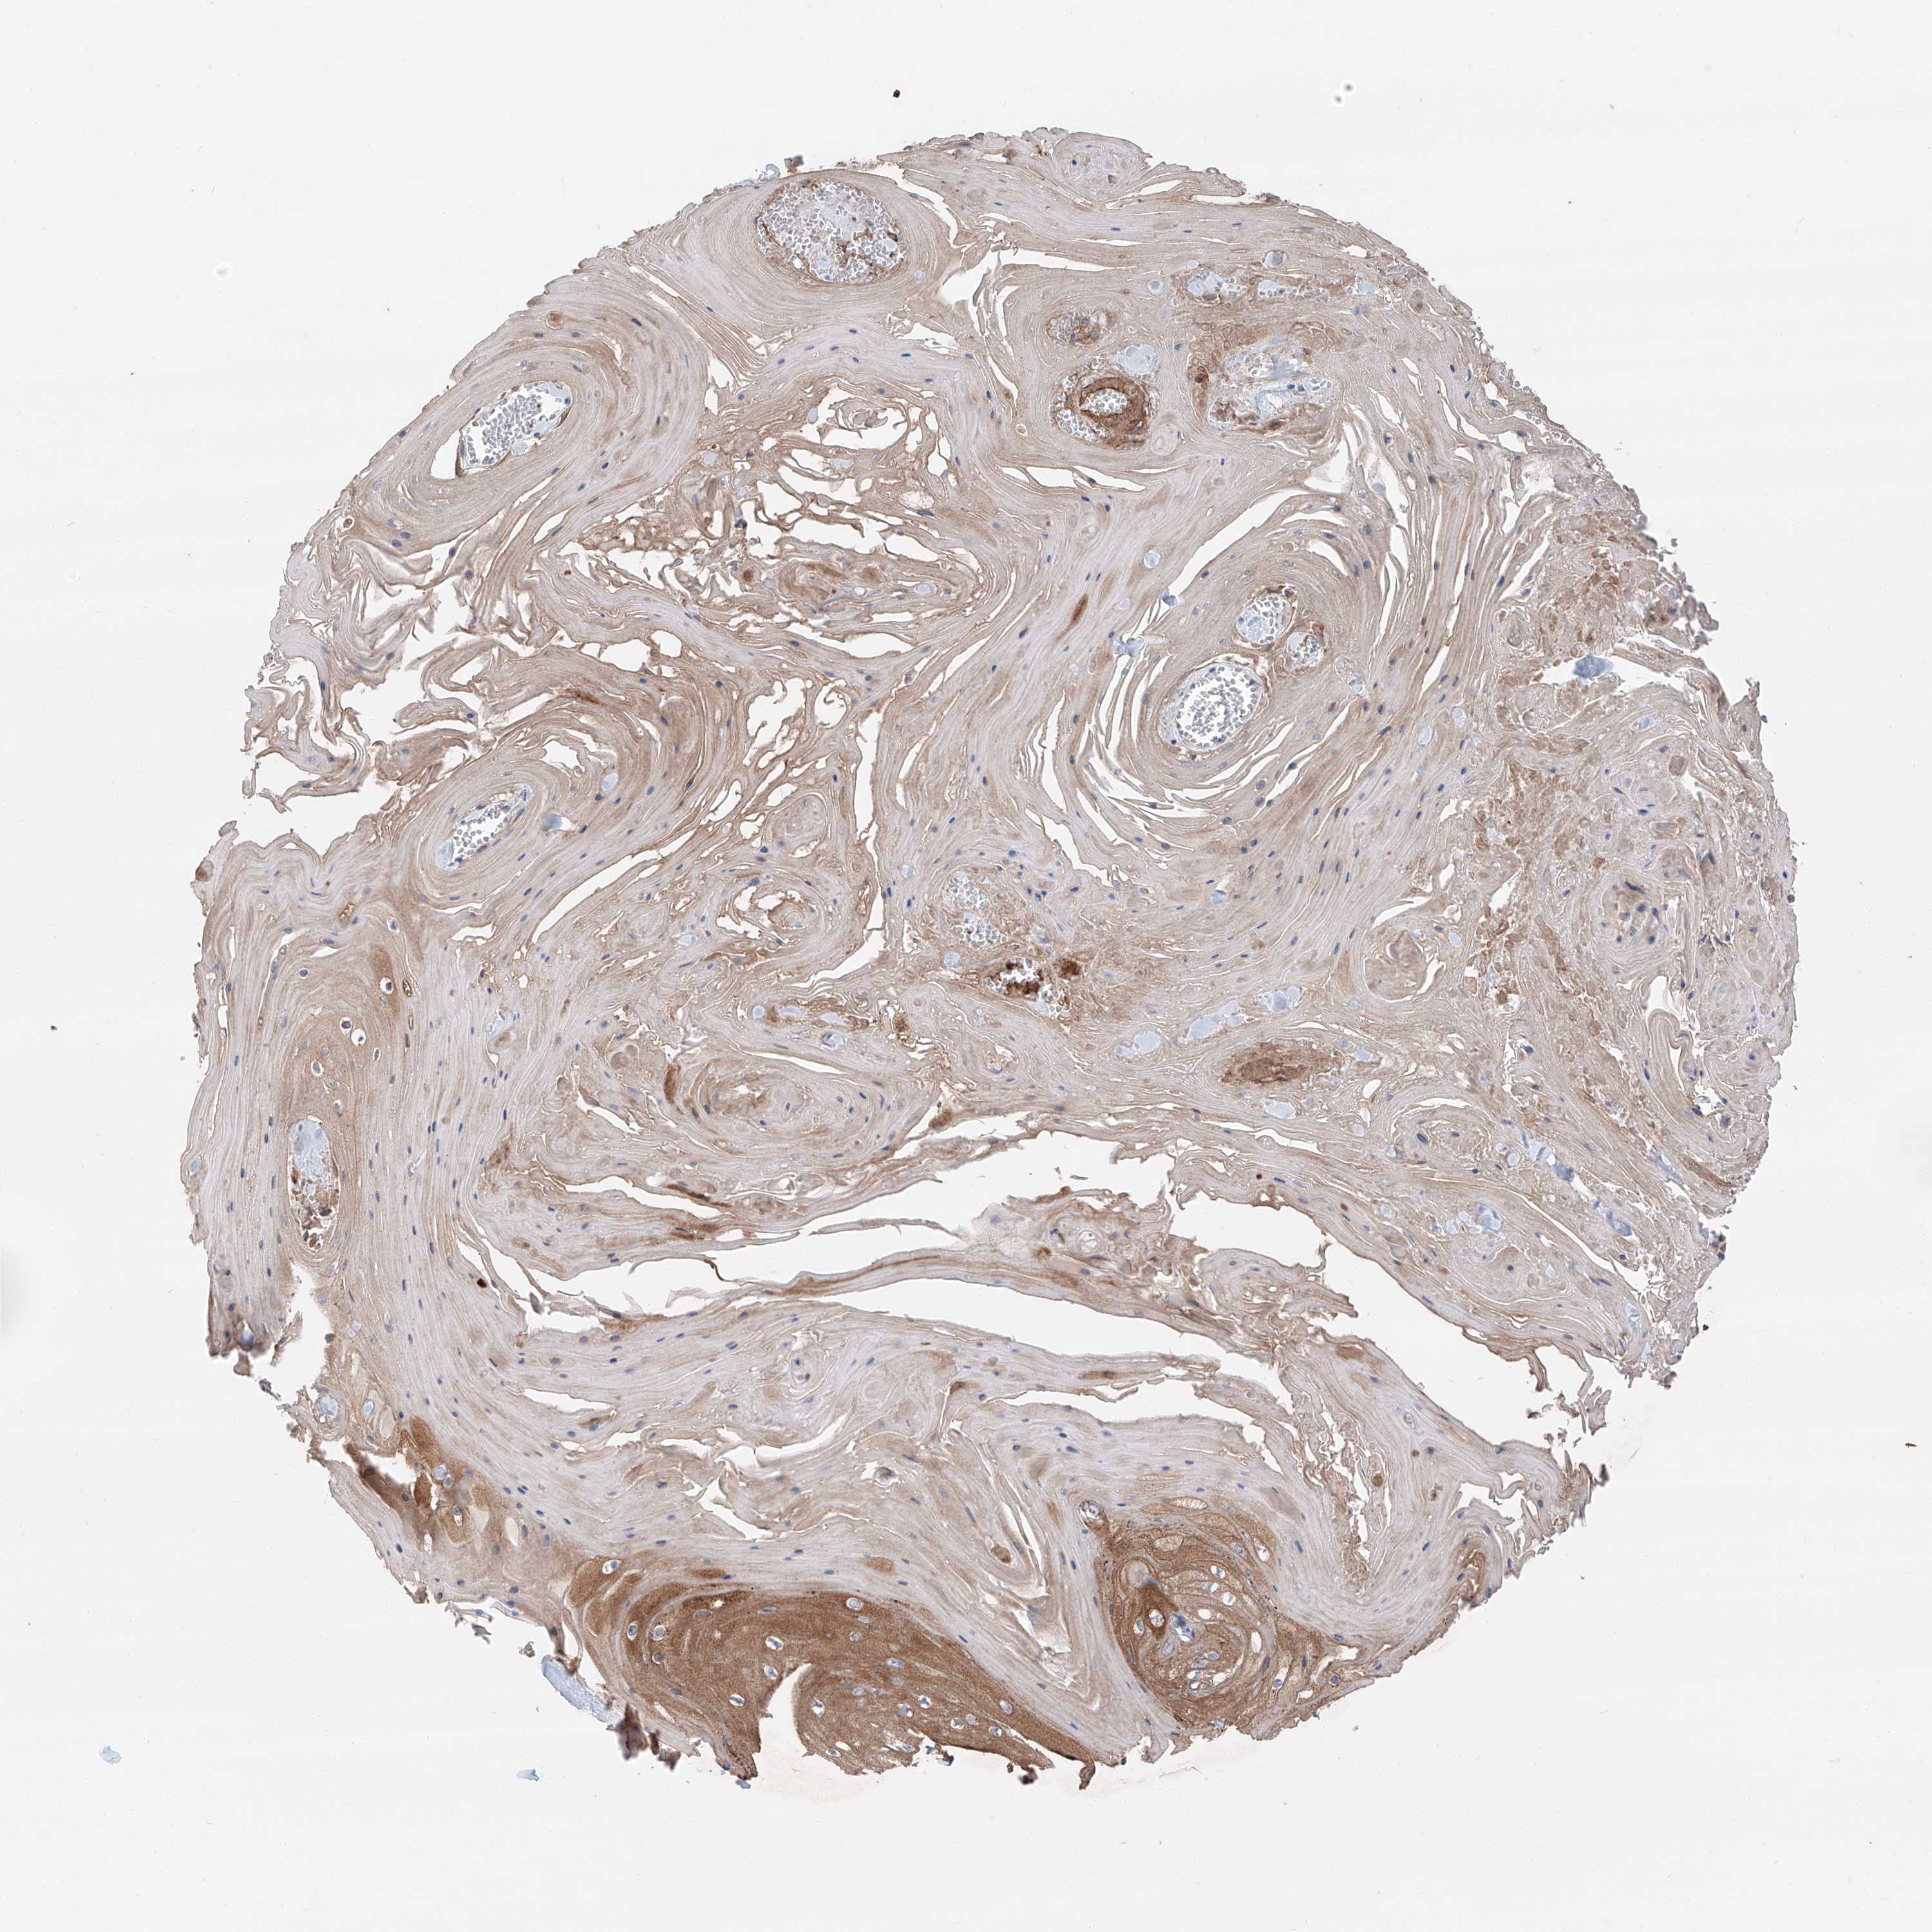

Basal cell and squamous cell cancer

SKIN CANCER - Protein expressioni

A mouse-over function shows sample information and annotation data. Click on an image to view it in a full screen mode. Samples can be filtered based on level of antibody staining by selecting one or several of the following categories: high, medium, low and not detected. The assay and annotation is described here.

Antibody stainingi

Antibody staining in the annotated cell types in the current human tissue is reported as not detected, low, medium, or high, based on conventional immunohistochemistry profiling in selected tissues. This score is based on the combination of the staining intensity and fraction of stained cells.

Each image is clickable and will lead to virtual microscopy that enables deeper exploration of all samples and also displays staining intensity scores, fraction scores and subcellular localization as well as patient and tissue information for each sample.

Antibody HPA031794

Staining

High

Intensity

Strong

Quantity

>75%

Location

Nuclear

Basal cell carcinoma